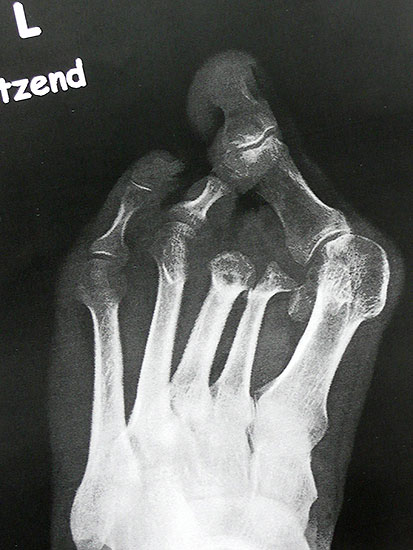

Es ist ungünstig, wenn wenige Kleinzehen lateral belassen werden. Das führt zum Kippen der Nachbarzehen oder zur Fehlstellung der verbliebenen Zehen (Abb. 18 - 20) und schließt eine optimale schuhtechnische Versorgung aus. Weitere Druckulzera sind zu erwarten. Die Großzehe kann als einzige Zehe belassen werden, wobei dann bisweilen die Arthrodese im Großzehengrundgelenk zur Stabilisierung ratsam ist (Abb. 21, 22).